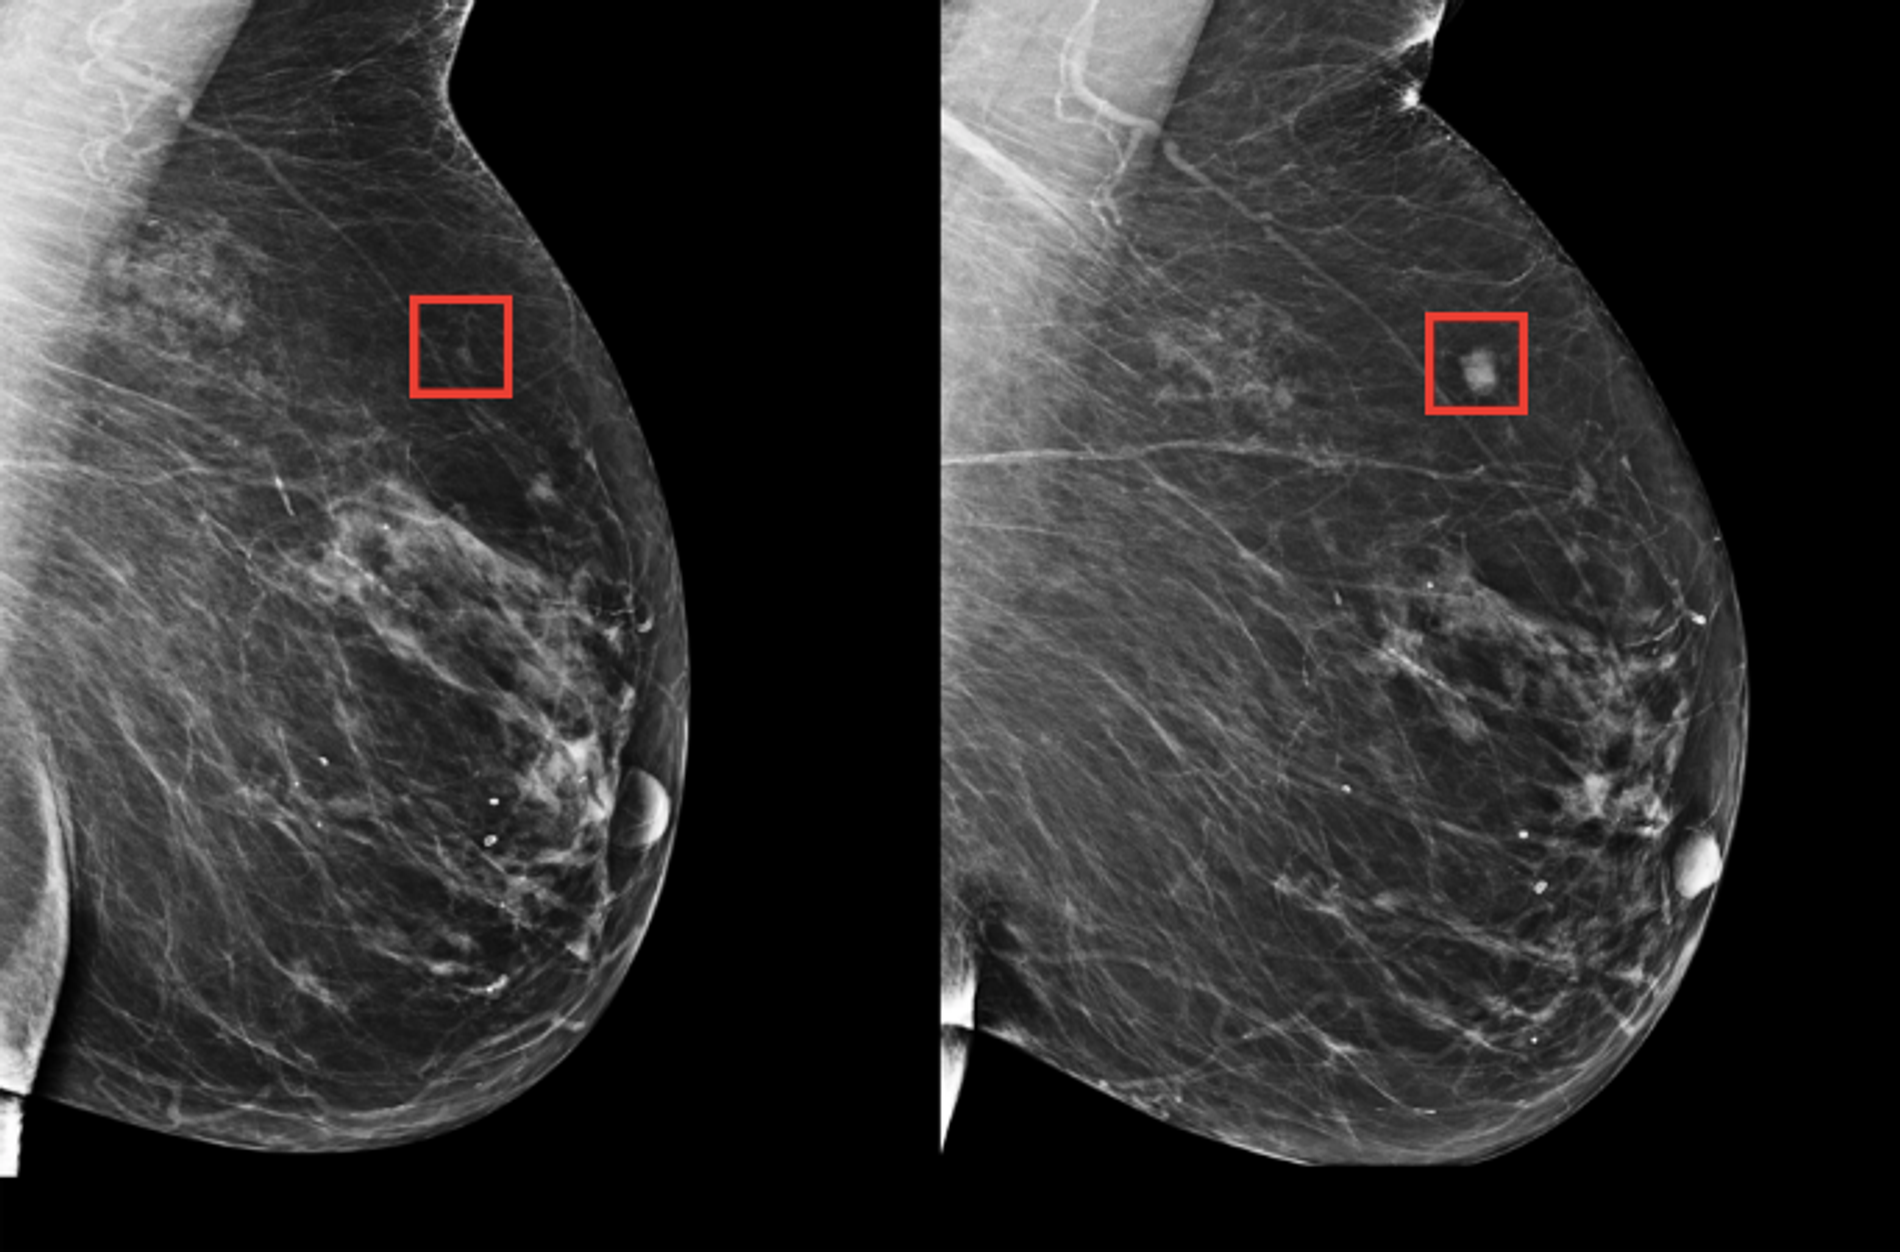

Durante octubre, mes internacional de concientización sobre el cáncer de mama, es habitual que laboratorios, clínicas y hospitales ofrezcan promociones en mastografías y ultrasonidos de mamas

Estas acciones fomentan una cultura de consumo informada, fortaleciendo la prevención y cuidado de la salud, y contribuyen a detectar de manera temprana cualquier anomalía mamaria.